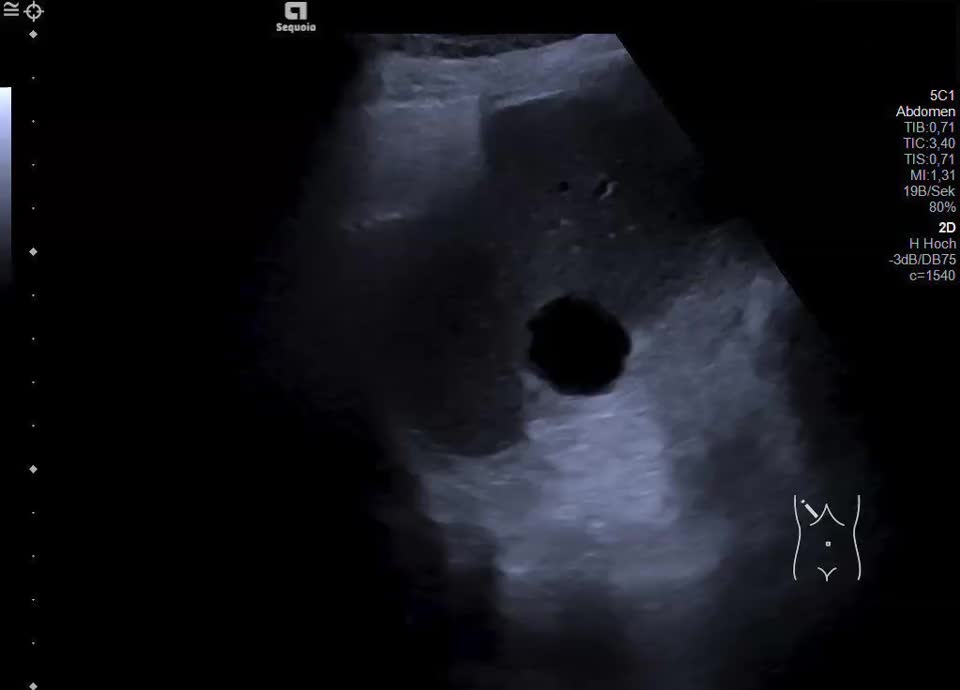

Es zeigt sich subkapsulär in Segment VI der Leber eine zystische Raumforderung mit durchgehendem Kapselreflex und hyperechogenem solidem Anteil. Der Befund ist nicht vereinbar mit einer blanden Zyste, sondern suspekt auf eine zystisch-solide Metastase. In der ergänzenden CEUS nehmen die soliden Anteile in der arteriellen Phase Kontrastmittel auf und zeigen in den portalvenösen sowie späten Phasen eine persistierende KM-Anreicherung ohne Washout. Zusätzlich finden sich eine noduläre Peritonealverdickung im Oberbauch sowie ein zystischer Ovarialtumor mit soliden Anteilen im rechten Unterbauch. In Zusammenschau der Befunde besteht der dringende Verdacht auf ein hepatisch und peritoneal metastasierendes Ovarialkarzinom.